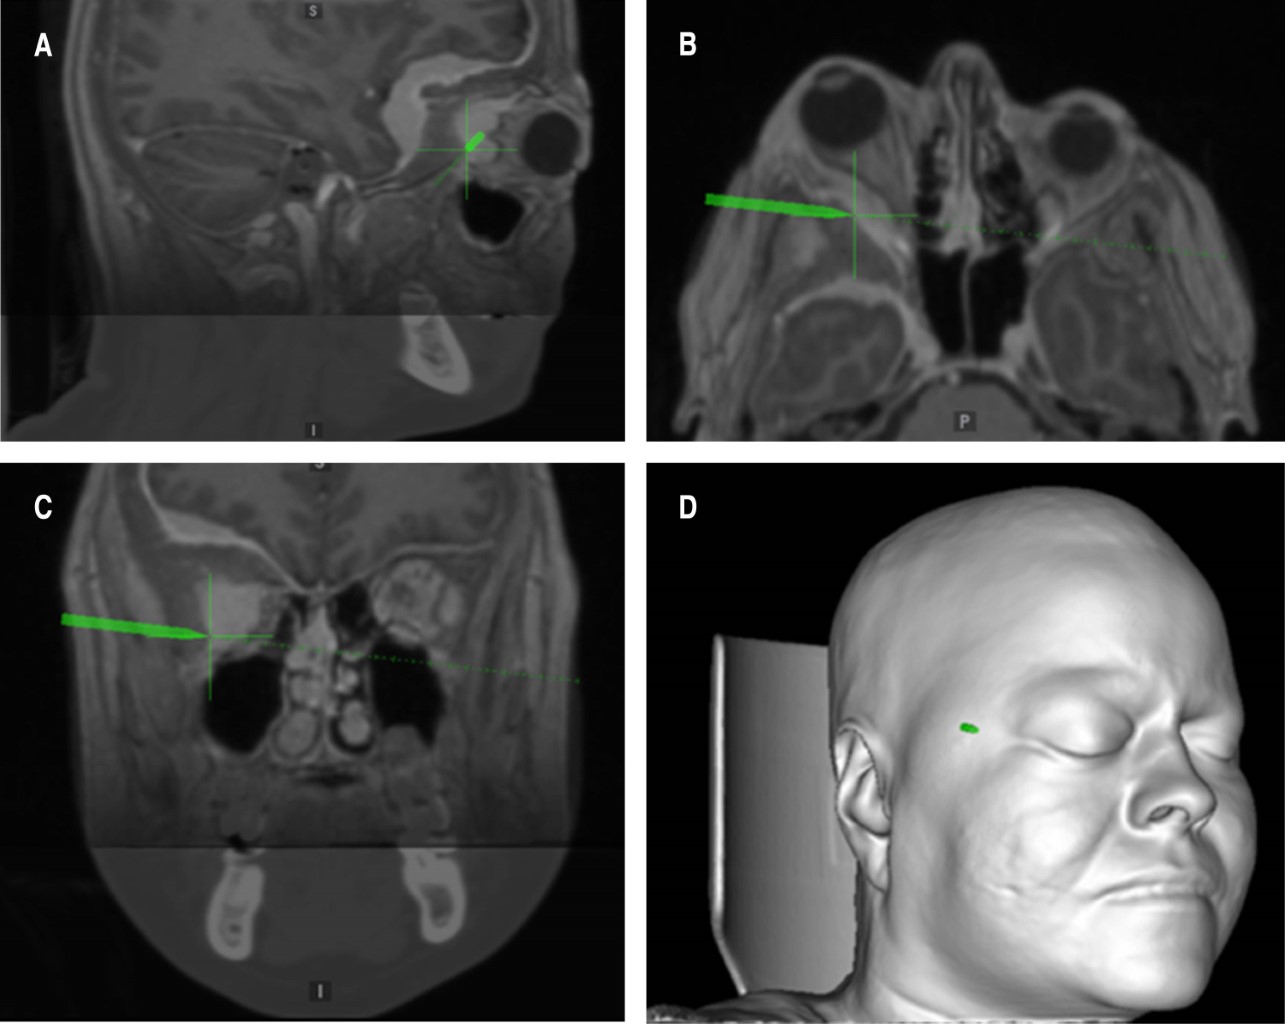

Se realiza incisión pterional ampliada, craniectomía frontotemporal con osteotomía órbito-cigomática derecha, descompresión de hendidura esfenoidal y agujero óptico, guiada por neuronavegación, resección de implante dural con componente tumoral óseo frontoorbitario (Simpson I) y descompresión orbitaria extraconal con plastia dural (Figuras 2 y 3).

Posterior a cirugía se realiza resonancia magnética simple y contrastada de control sin evidencia de tumor residual, por lo que no ameritó radioterapia adyuvante, manteniéndose en vigilancia estrecha y libre de actividad tumoral a dos años de seguimiento y se lleva a cabo reconstrucción de defecto craneal con placa preformada en 3D de metilmetacrilato (Figura 4).

Figura 2

Figura 3

Figura 4